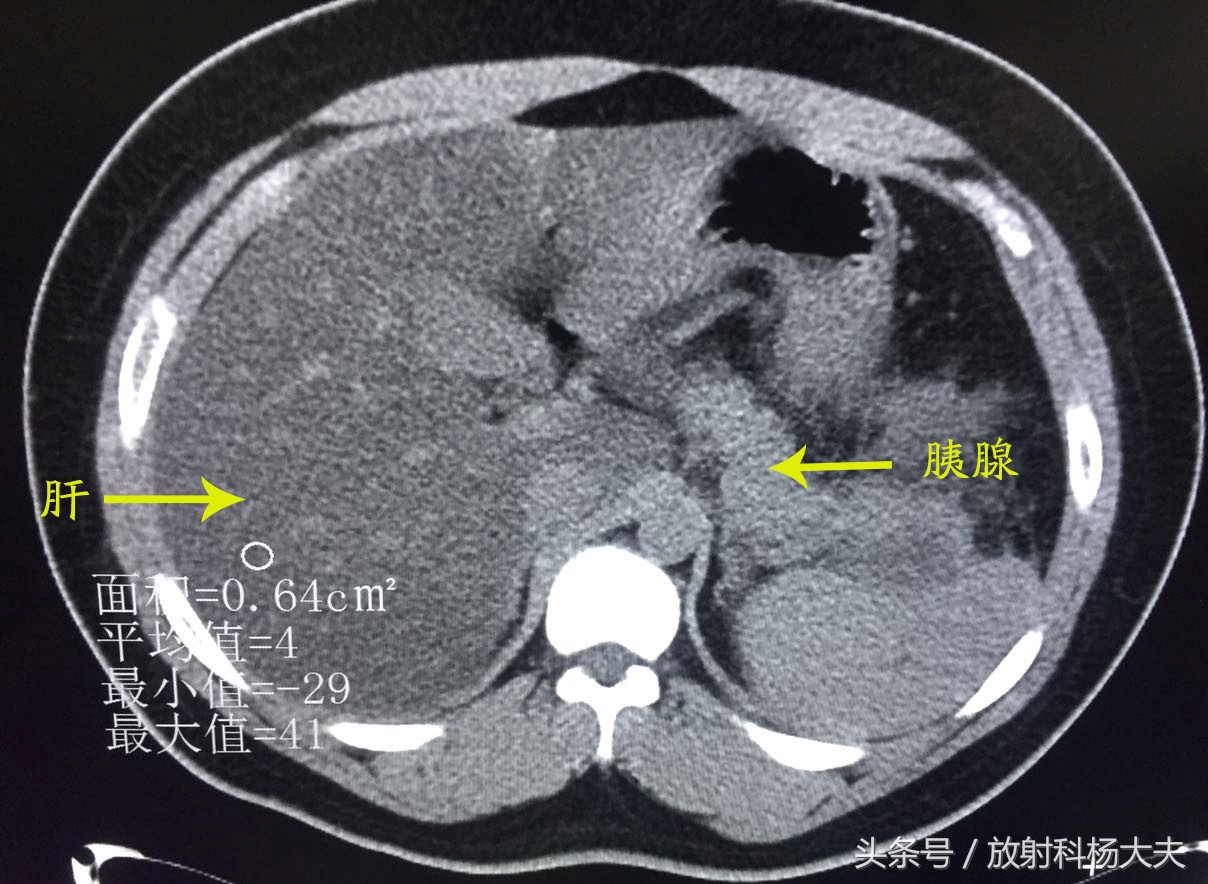

我即刻查阅了他既往的片子,果然,一年前因为腹痛就诊过,CT检查如下:

CT图像可见肝脏密度弥漫性减低,明显低于同层面脾脏密度,胰腺饱满,周围可见渗出样改变---急性胰腺炎伴重度脂肪肝。